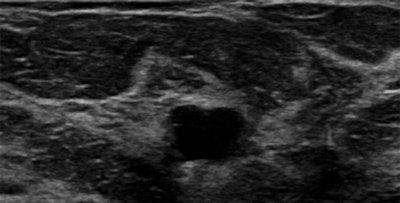

The study included 340 women with 353 lesions that were found at screening mammography (198) or ultrasound (155). The lesions were rated BI-RADS category 4 after appropriate conventional workup between June 2010 and January 2013. All of the women underwent standard dynamic contrast-enhanced MR imaging (Radiology, February 2015, Vol. 274:2, pp. 343-351).

Among the 198 mammography findings, 71 were masses, 34 were asymmetric densities, 15 were architectural distortions, and 78 were clustered microcalcifications. Of the 155 ultrasound findings, 115 were masses and 40 were nonmass lesions.